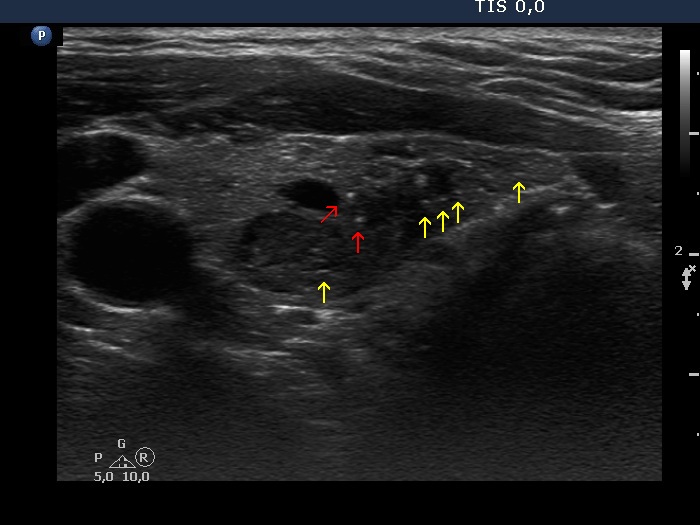

Consecutive patients with the final diagnosis of Hashimoto's thyroiditis - case 38 (1617) (ultrasonographic picture 5b)

Left lobe, longitudinal scan. The pale echogenic lines and granules (yellow arrows) are presentations of connective tissue. On the other hand, the interpretation of the more bright granules (red arrow) is more difficult. On this view they might be microcalcifications.